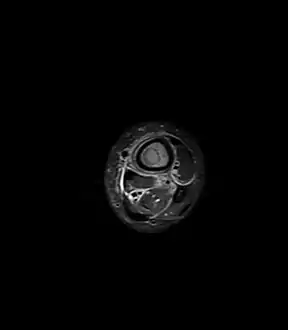

Periostial reaction along the medial cortex indicates an aggressive lesion. Neoplasm such as Ewing sarcoma and osteomyelitis could both have this plain radiographic appearance. Staphylococcus was recovered at surgery. Fat saturated STIR (short tau inversion recovery) image showing hyperintense edema in the calf musculature, marrow edema, and subperiosteal pus. The intramedullary abscess cavity is hyperintense as well.

Fat saturated STIR (short tau inversion recovery) image showing hyperintense edema in the calf musculature, marrow edema, and subperiosteal pus. The intramedullary abscess cavity is hyperintense as well. Coronal fat suppressed STIR image showing, bone marrow and subcutaneous edema as well as subperiosteal edema. The thin hypointense rim surrounding the intramedullary collection represents the reactive interface between the abscess and the body's attempt to wall it off.

Coronal fat suppressed STIR image showing, bone marrow and subcutaneous edema as well as subperiosteal edema. The thin hypointense rim surrounding the intramedullary collection represents the reactive interface between the abscess and the body's attempt to wall it off. Axial T1-weighted MRI pre-contrast enhancement showing that the intramedullary collection is T1-hyperintense suggesting proteinaceous viscous fluid consistent with infection.

Axial T1-weighted MRI pre-contrast enhancement showing that the intramedullary collection is T1-hyperintense suggesting proteinaceous viscous fluid consistent with infection. Axial T1-weighted fat-saturated MRI image following IV gadolinium contrast demonstrating the intramedullary lytic area seen on radiography to be ring enhancing consistent with a purulent fluid collection. Extensive circumferential periosteal enhancement is noted. There is also substantial bone marrow enhancement.